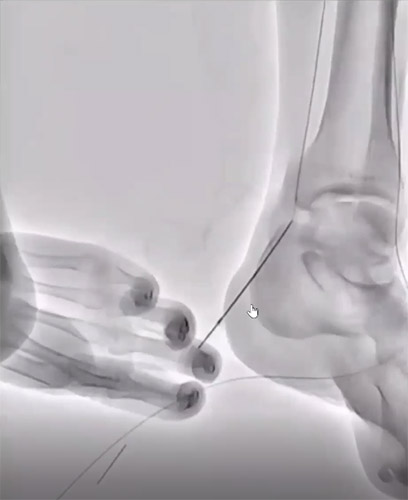

PTAからワイヤーを18Gの針で穿刺し【図5】、プルスルーを実施。【図6】高度石灰化のため、プルスルーしたワイヤーを使用して穿刺針でプリパレーションを行い、4Frマイクロパンクチャーシースを挿入しPTA閉塞部をCrosperioRX 2.5-200mmで拡張しPTAの開存を確認。【図7】